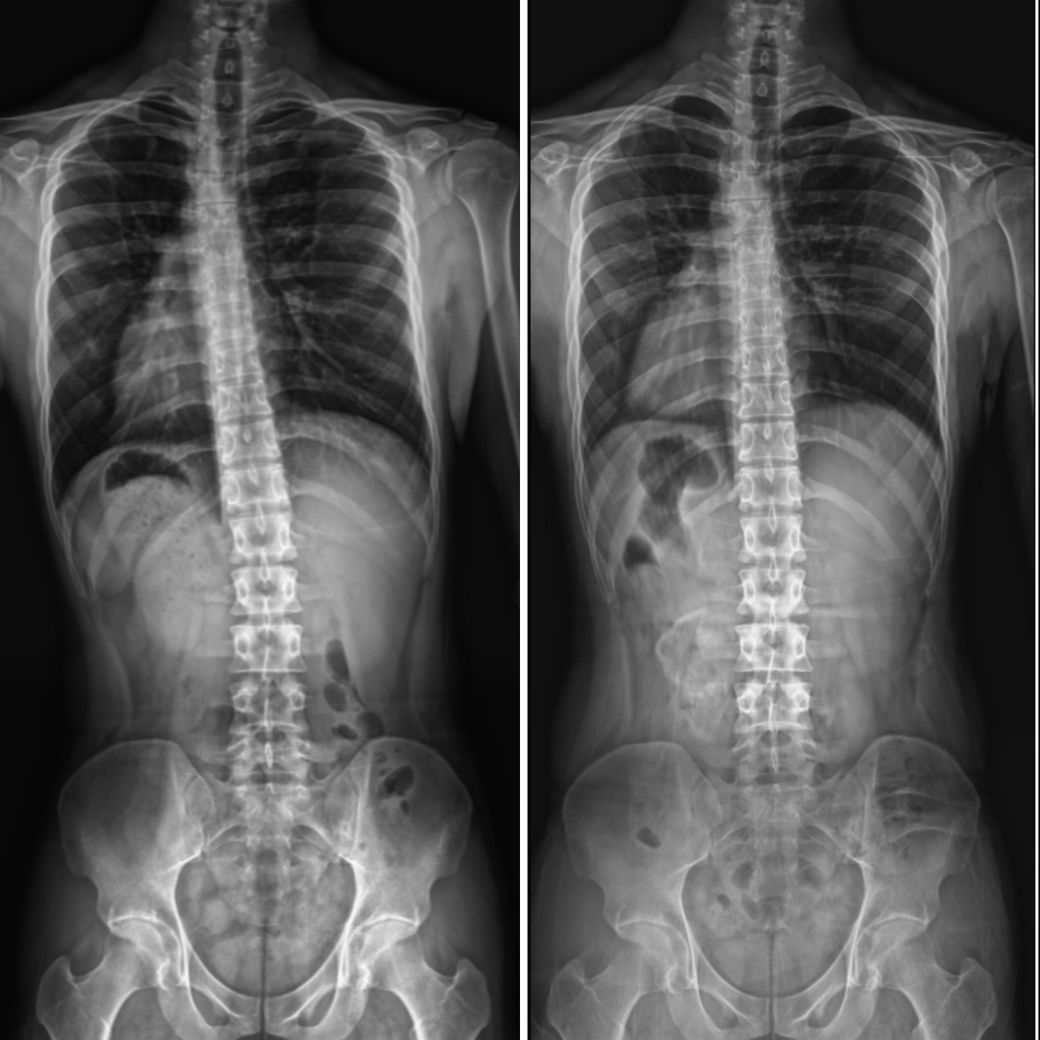

왼쪽이 1년전 오른쪽이 얼마전 찍은 건데(같은 병원에서 찍었습니다)

제가 이 사이에 아무런 교정을 안받았는데

측만증이 자연적으로 호전되어 있어요

성인의 뼈는 굳어서 쉽게 움직이지 않는걸로 아는데

제 몸이 특이한건가요?

제가 특수한 케이스인지 아니면 원래 이런건지 궁금합니다

성인 측만증은 보통 자연 호전이 드물지만 체형 변화나 자세 개선으로 일부 개선될 수 있습니다. 검사 시 자세나 촬영 각도 차이도 호전처럼 보일 수 있습니다 특별한 치료 없이 변화가 있다면 생활습관이나 운동 등이 영향을 줬을 가능성도 있습니다! 정확한 판단은 담당 전문의와 상담해 확인하는 것이 좋아요!